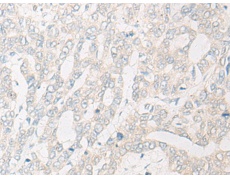

IHC positive control:

Human gastric cancer; Human liver cancer

IHC Recommend dilution:

20-100